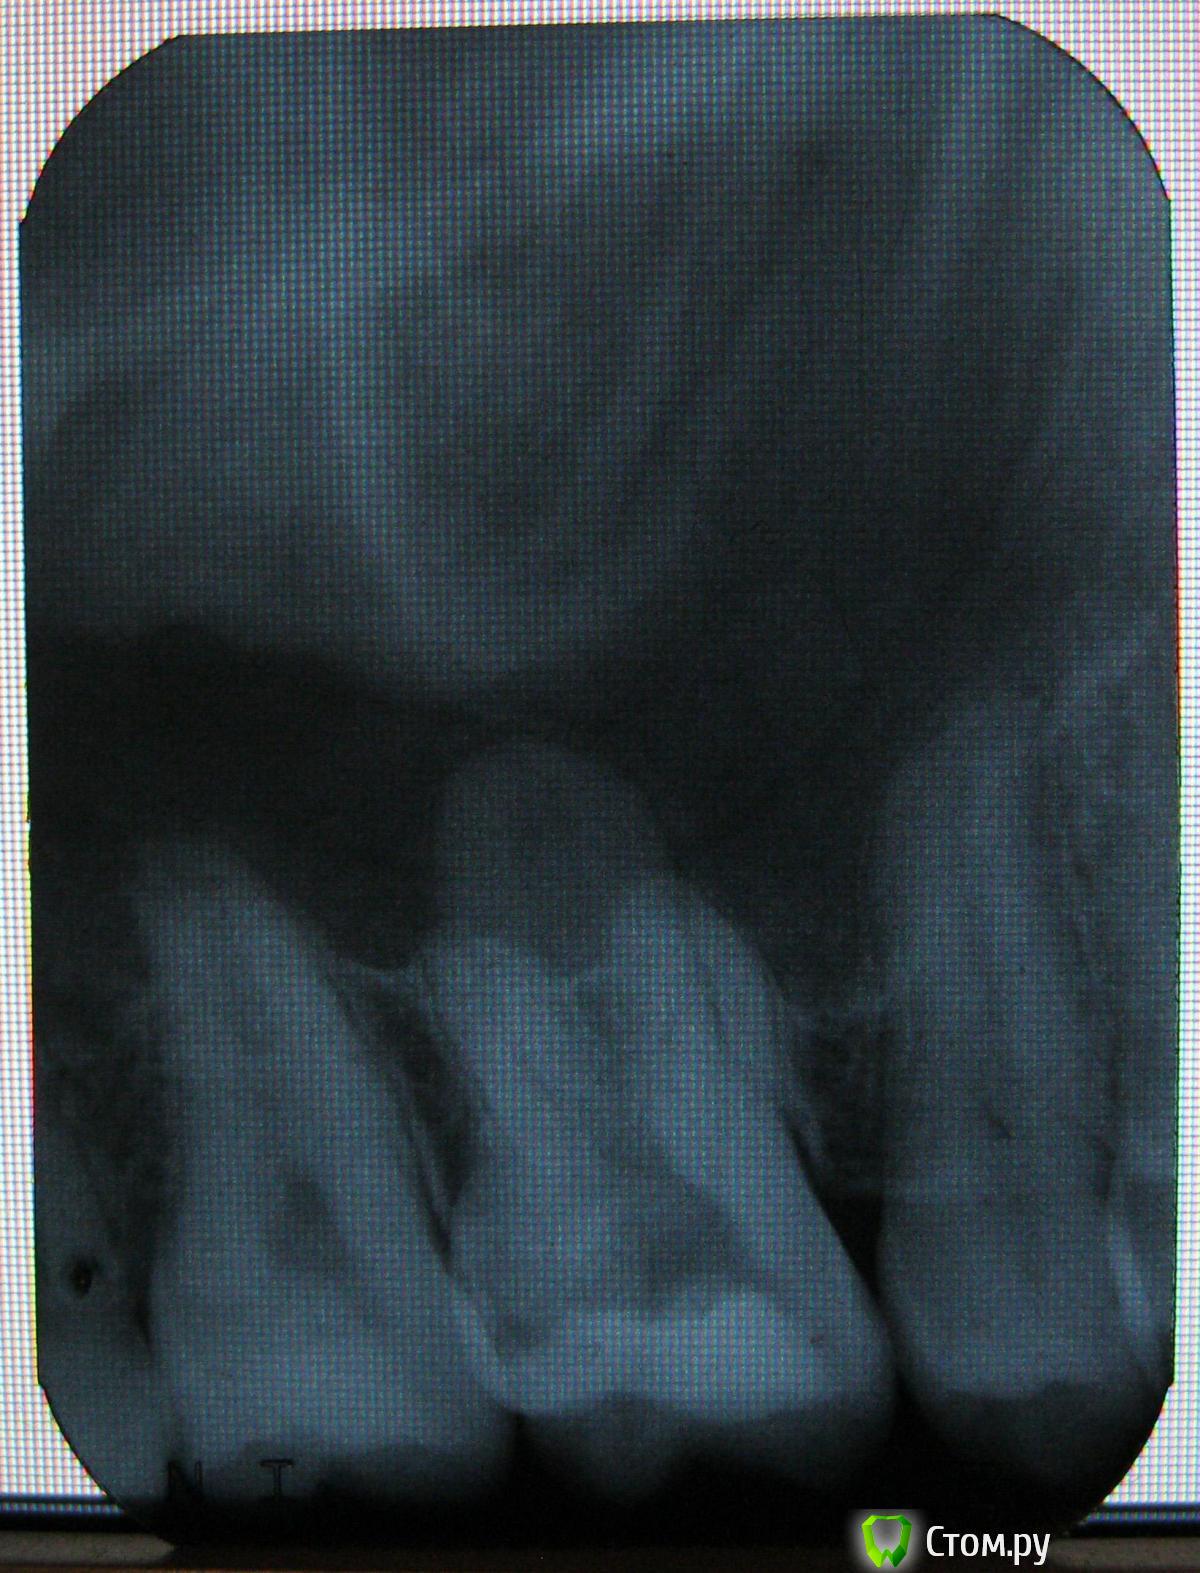

b69 Опубликовано 7 ноября, 2011 Поделиться Опубликовано 7 ноября, 2011 Обнаружили пульпит в зубе, врач поставил Депульпин. После этого, через несколько дней, сделал снимок. Вопрос, что за область, отличающегося оттенка, над средним зубом на снимке? Ссылка на комментарий

Stomart Опубликовано 7 ноября, 2011 Поделиться Опубликовано 7 ноября, 2011 (изменено) Это третий корень Изменено 7 ноября, 2011 пользователем Stomart Ссылка на комментарий